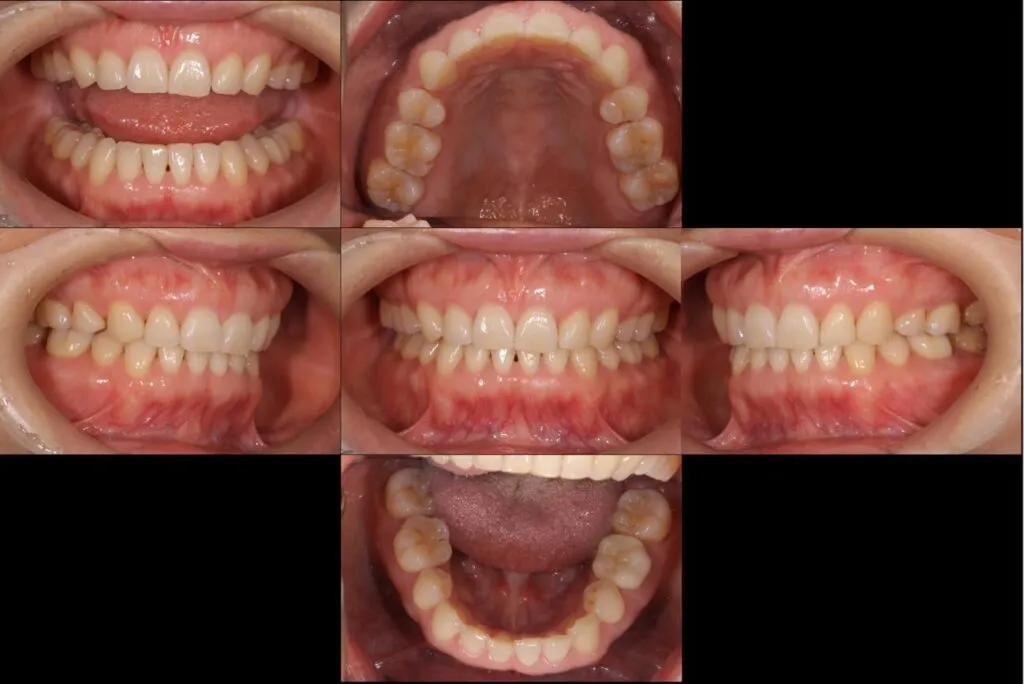

症例

患者様のお悩み | 左下が痛くて噛めない |

|---|---|

治療法・使用素材 | 自費根管治療・補綴処置・オールセラミック |

患者様の年代 | 30代 |

治療開始年齢 | 36歳 |

治療にかかった期間 | 6ヶ月 |

性別 | 女性 |

この治療のリスクについて | 病態が改善しないかもしれない |

治療にかかった費用 | 30万 |

治療前

治療後